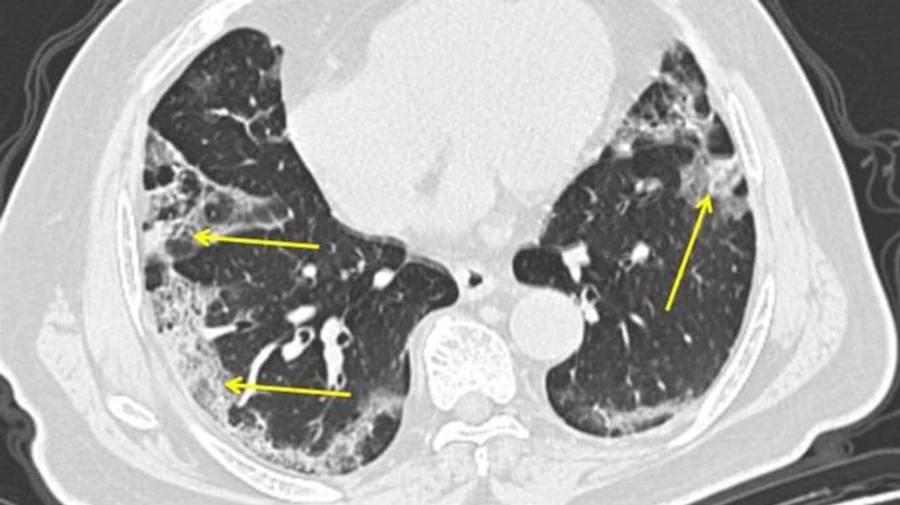

За неделю с 5 по 11 октября в Украине диагностировали 22,4 тысячи пневмоний, с середины июля этот показатель вырос в 5 раз.

Прямая речь Степанова: "У нас существенно увеличилось количество людей с пневмониями. За прошедшую неделю - это 22 400 человек. Для понимания: за неделю с 13-го по 19-е июля у нас всего было 4 234 пневмоний .Вы видите, что более чем в 5 раз (выросло количество)".